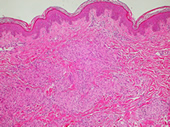

4歳以前に発症する、皮疹(紅潮を伴う充実性丘疹)、関節症状(腱鞘炎)、眼症状(全眼球性ぶどう膜炎)を3主徴とし、組織学的には非乾酪性類上皮細胞肉芽腫、巨細胞性肉芽腫を特徴とする。成人のサルコイドーシスに特徴的とされる肺門部リンパ腫脹は認めない。